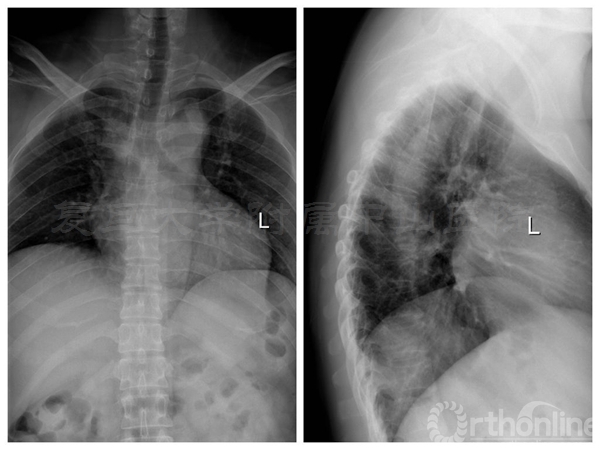

术前胸椎正侧位X线:未见明显骨质异常

术前三维CT:T7/8水平可见椎管内占位

术前MRI:T7-8水平椎管内占位伴脊髓变性,脊膜瘤可能的大